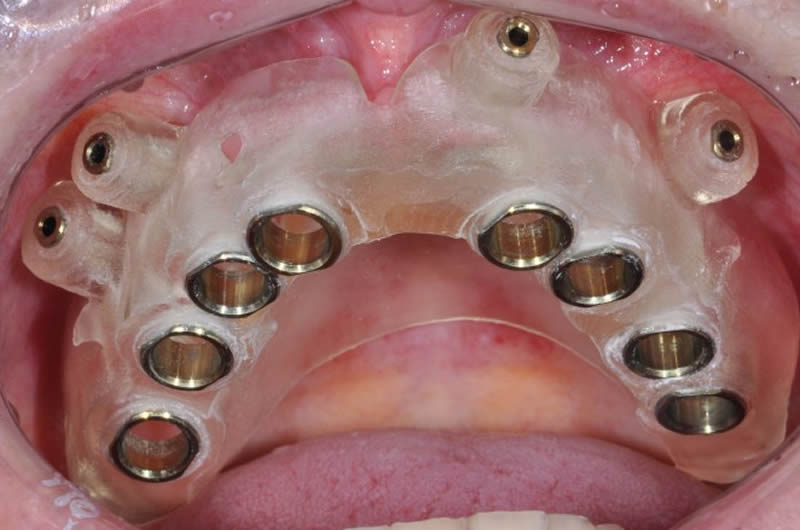

Guia Cirúrgica Prototipada

Guia Cirúrgica Prototipada em Boca